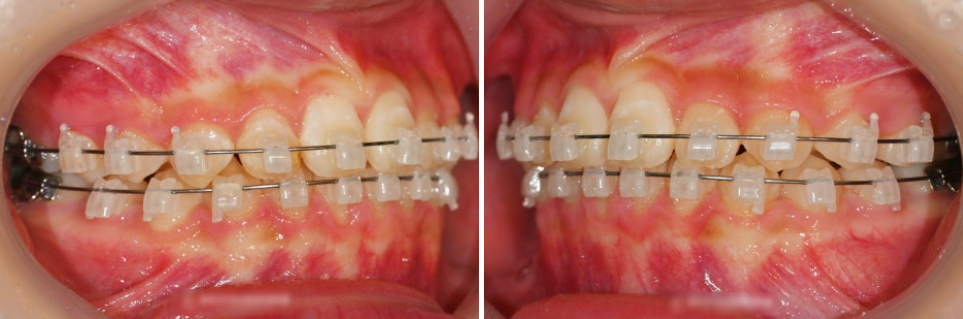

클라리티 브라켓으로 부착한 모습입니다.

이렇게 부착한 뒤의 모습을 보았을 때

특수 코팅 처리가 되어 있어 심미성이 뛰어납니다.

또, 가까이서 얘기를 나눌 때도

크게 티가 나지 않는 장치라 말씀드릴 수 있습니다.